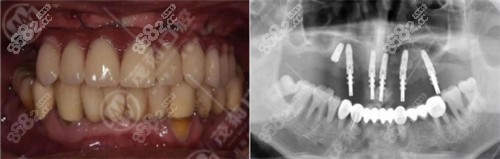

口腔种植牙怎么样呢?

口腔在种植牙的设备上比较齐全,有种植前的意大利NEWTOMN锥形束三维影像系统、韩国口腔专用DCT,德国Sirona数字化全景机,还有种植牙用的奥地利WH种植机,这些设备都是国内外目前比较火的几款设备。

在种植体上,口腔有韩系植体、瑞典诺贝尔(Nobel Guide)、瑞士ITI和德国ICX、德国BEGO等种植系统的授权认证,大家大可不必担心自己的植体有假。

当然,要说一台种植牙的手术,更核心的还是医生方面了,设备、植体都是辅助医生用的,技术好的医生可以使得整个种植手术过程更加顺利。

其中的林崇韬医生就是一位由24年经验的口腔博士医生,对于半口全口的无牙颌种植比较擅长。还有占美红医生,是口腔的总院长,由20余年的临床经验。等等~